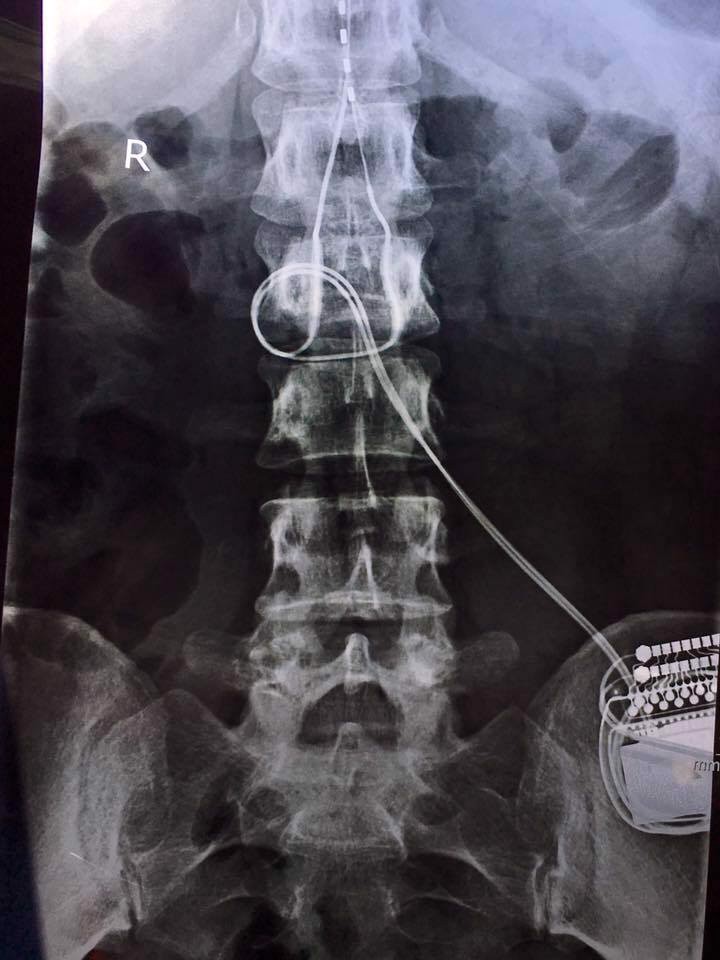

5. Having had to endure spinal cord surgery to implant a Spinal Cord Stimulator from the Cleveland Clinic, for my CRPS, and can honestly say that I’m a literal cyborg